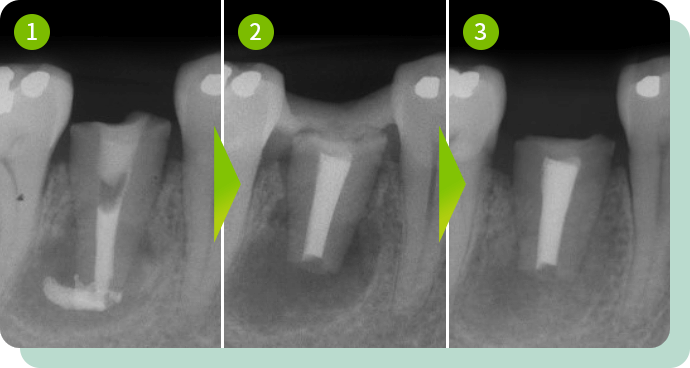

移植した例

使っていない歯を移植

一番奥の歯は反対側の奥歯を移植し、前の歯は矯正で引っ張り上げて機能させています。

このように、歯牙移植と矯正治療を組み合わせた治療により、口腔内の機能を回復させていく治療も可能です。

リスク:疼痛・出血・抜歯時・歯を動かす際に伴う痛みなど

費用:保険適応(症状やケースに応じて適応となります)